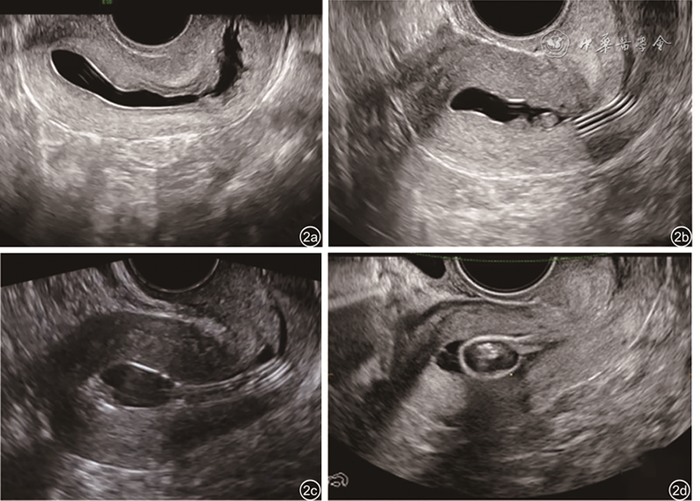

图2 新型造影管与传统造影管置管超声声像图。图a为新型造影管置管,水造影宫腔完整显示;图b为新型造影管置管,宫腔水造影发现宫颈内口息肉;图c为传统造影管置管,宫腔被球囊及造影管遮挡;图d与图b为同一患者,使用传统造影管置管,宫颈内口息肉被球囊遮挡